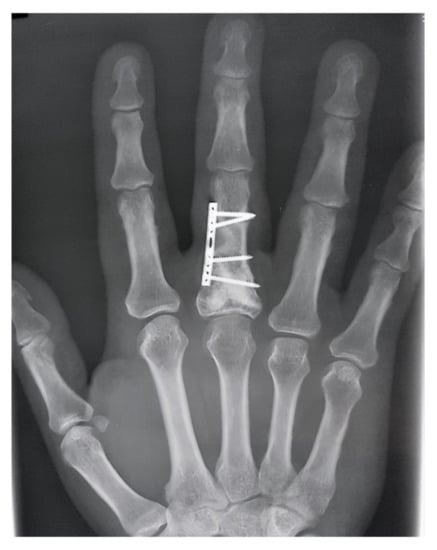

In the other seven cases, the bone defects were filled with injectable bone substitutes based on chitosan (k-IBS®). K-IBS® is presented in prefilled syringes with the ready-to-use bone substitute, so the bone substitute does not need any prior preparation before use. Osteosynthesis was performed with low profile miniplate and screws only in cases that presented signs of bone instability after tumor resection (Figure 2). Protected active and passive movement in the dynamic splint was performed on the 5th postoperative day in all cases.

Figure 2. Enchondroma of the first phalanx treated by curettage and injectable bone substitute. (A)—Immediate postoperative aspect of bone defect filled with injectable bone substitute and miniplate, (B)—Intraoperative application of k-IBS® substitute, (C)—miniplate-kit and prefilled ready-to-use syringe with bone substitute.